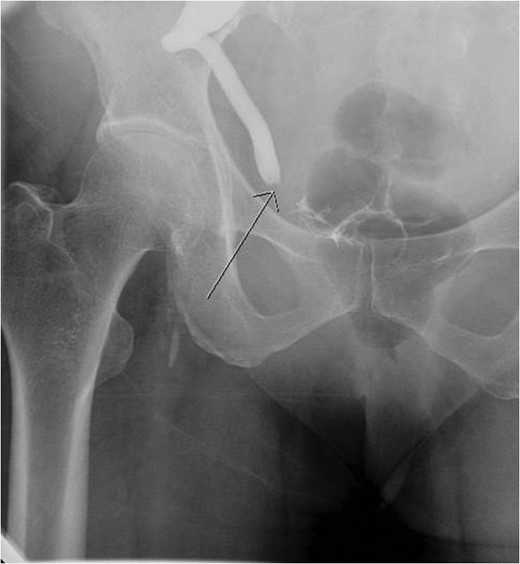

Intraoperative images depicting the tumor at the ureterovesical junction.